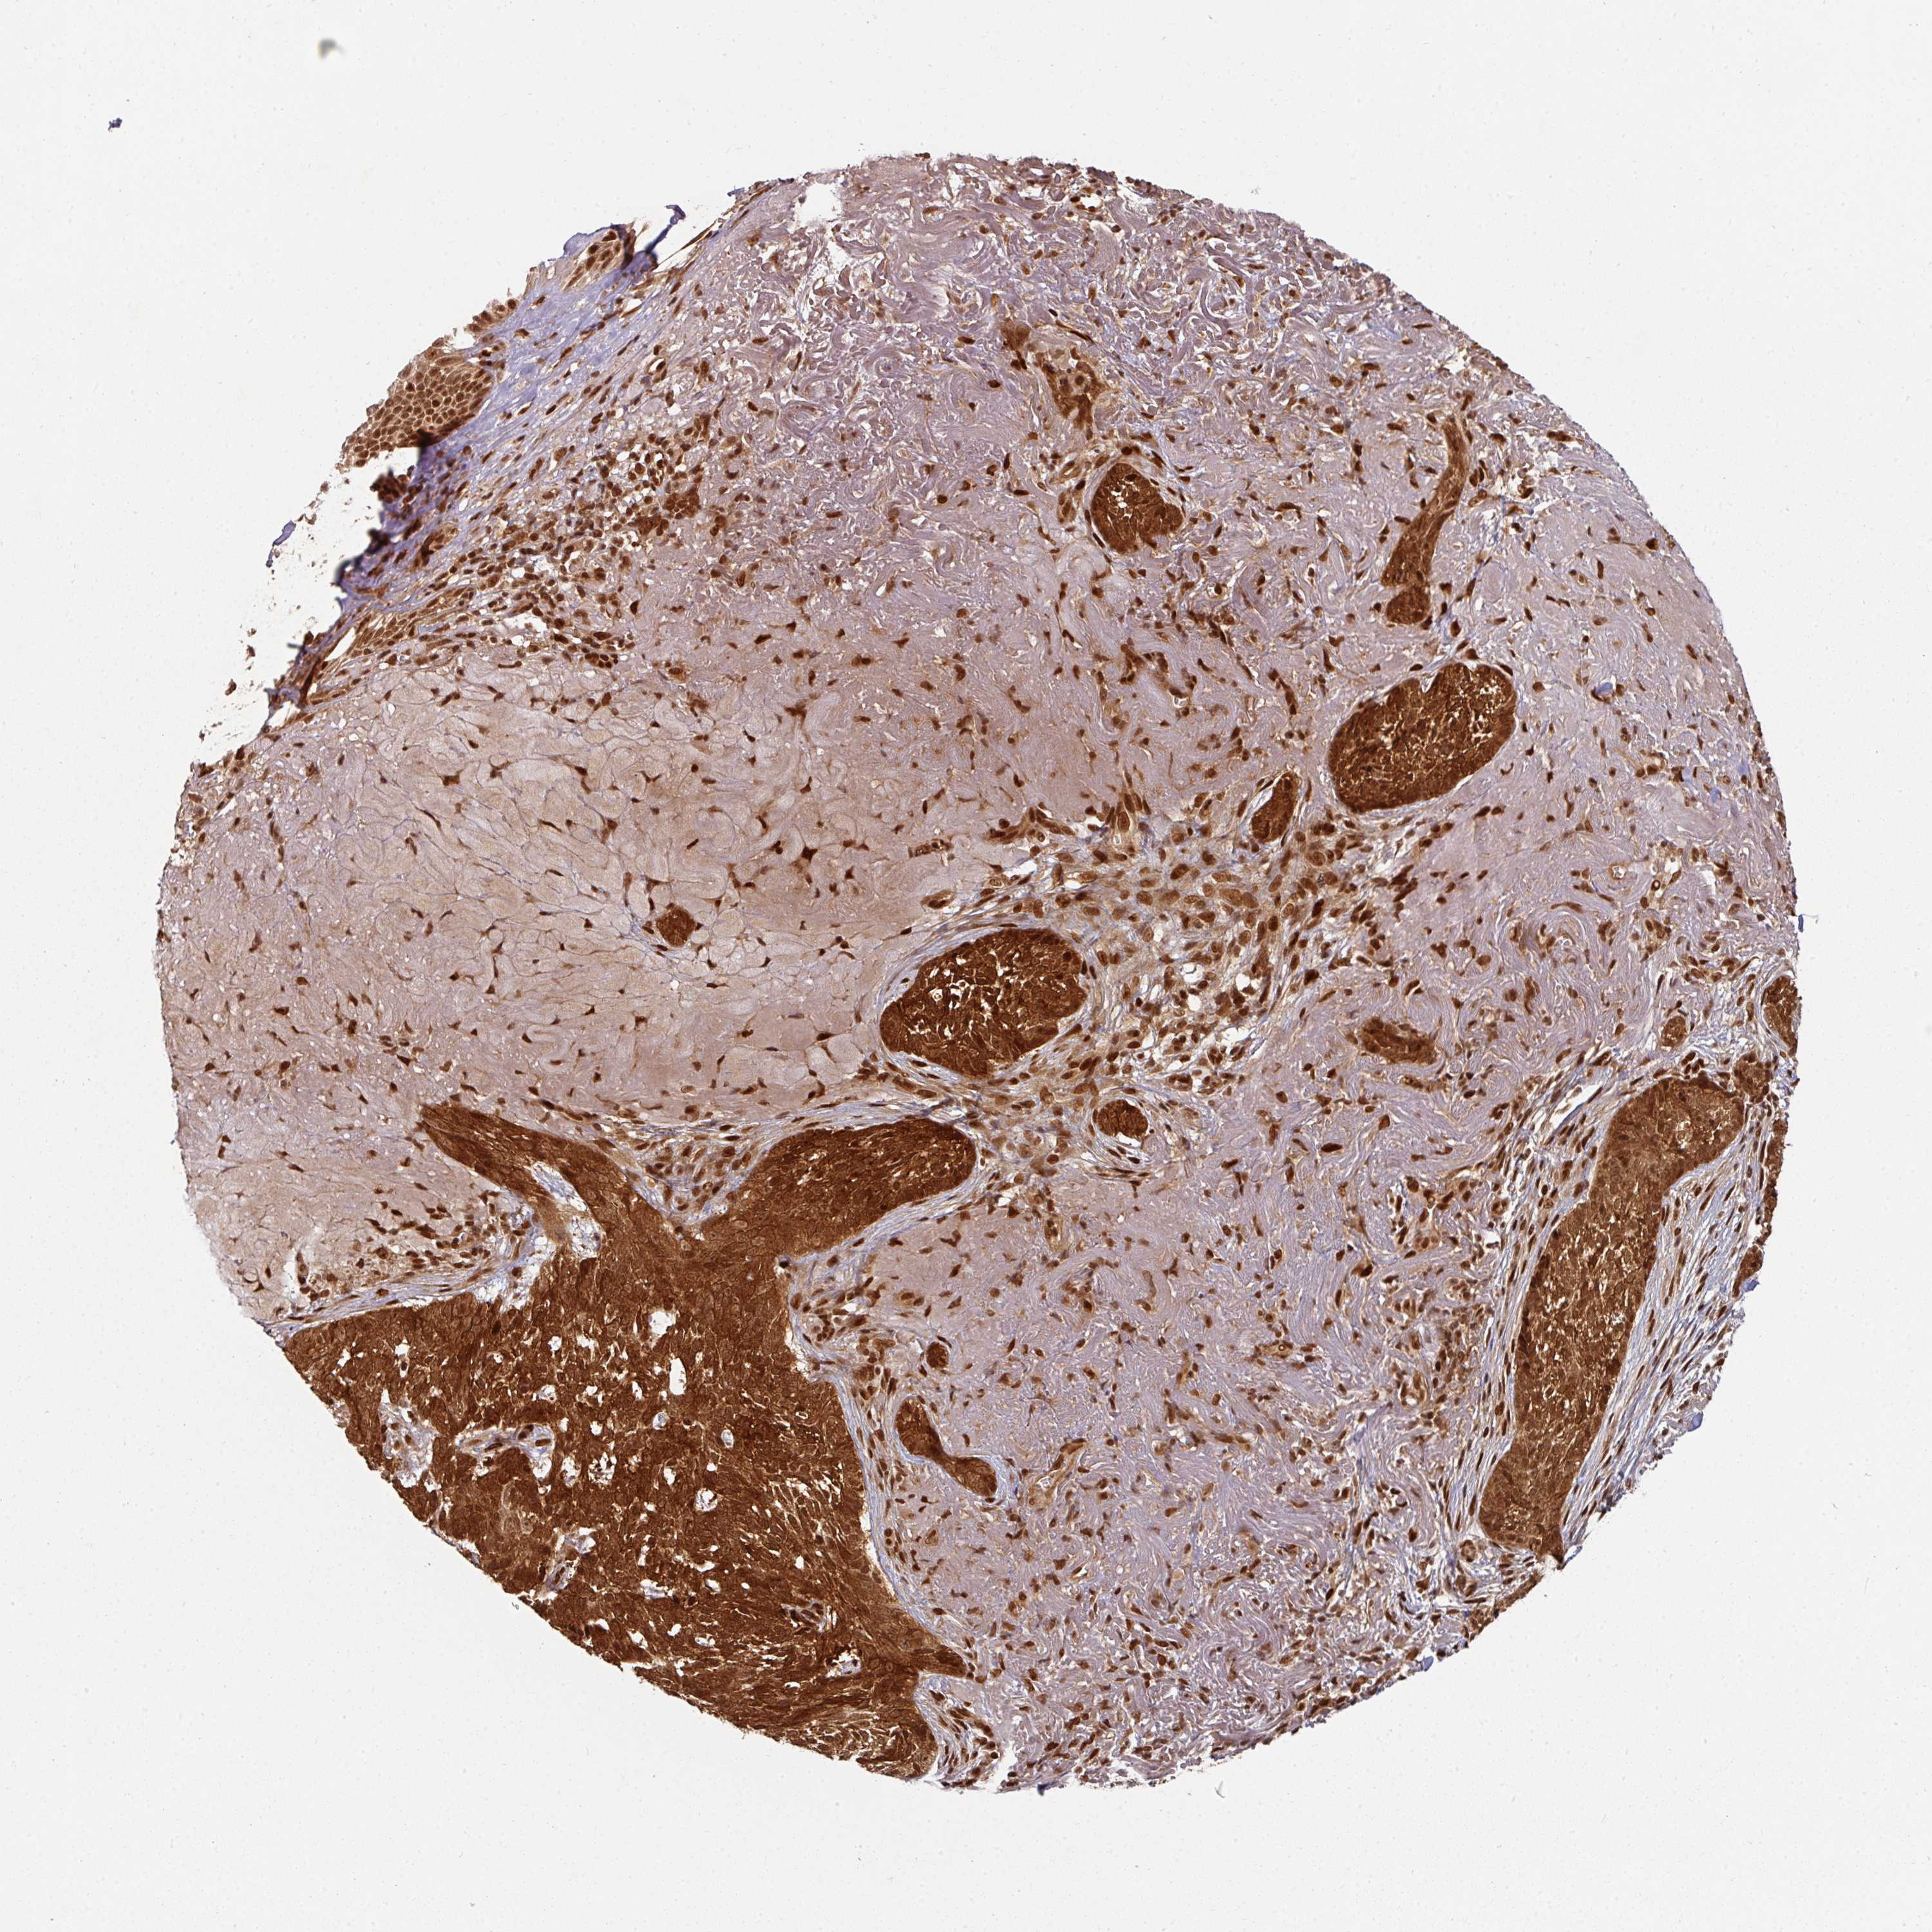

SKIN CANCER - Protein expressioni

A mouse-over function shows sample information and annotation data. Click on an image to view it in a full screen mode. Samples can be filtered based on level of antibody staining by selecting one or several of the following categories: high, medium, low and not detected. The assay and annotation is described here.

Antibody stainingi

Antibody staining in the annotated cell types in the current human tissue is reported as not detected, low, medium, or high, based on conventional immunohistochemistry profiling in selected tissues. This score is based on the combination of the staining intensity and fraction of stained cells.

Each image is clickable and will lead to virtual microscopy that enables deeper exploration of all samples and also displays staining intensity scores, fraction scores and subcellular localization as well as patient and tissue information for each sample.

Antibody HPA048161

Squamous cell carcinoma, NOS